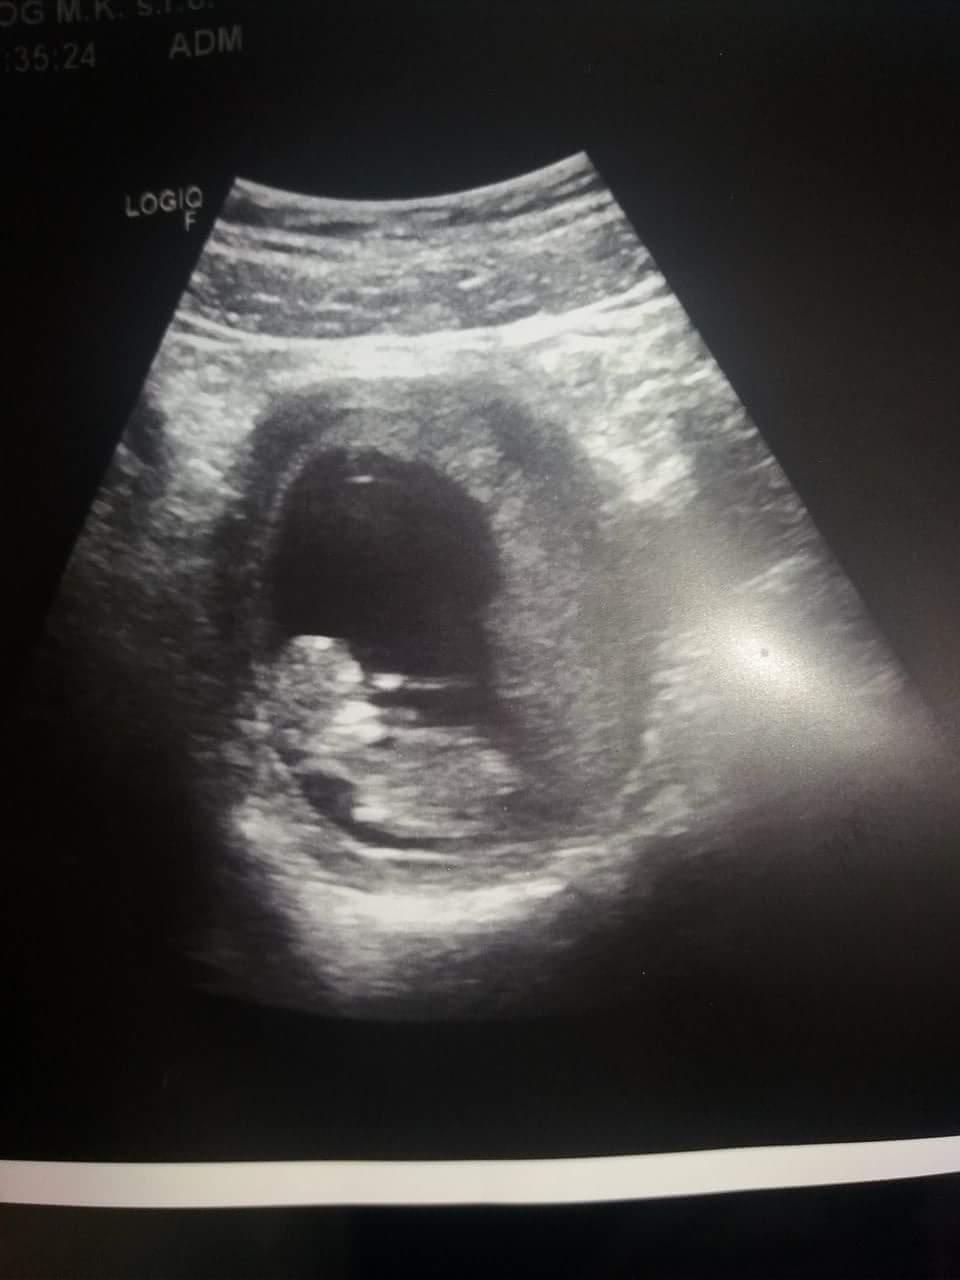

Ahojte.sestricka mi povedala,ze som v 13 tom tyzdni a doktorka na sone hovori,ze je mebsie na 11 ty tyzden.nevedia asi presnejsi termin.doktorka povedala,ze je nisko polozene pri konecniku.a ze je za maternicou.a tym padom nevidi organy.srdiecko bije,babätko je aktivne ale ze uz velmi davno tak nemala pacientku,ze nevedela v tomto stadiu vidiet organy a tak.je to nehaky problem?nieco zle?tu je aktualna fotka